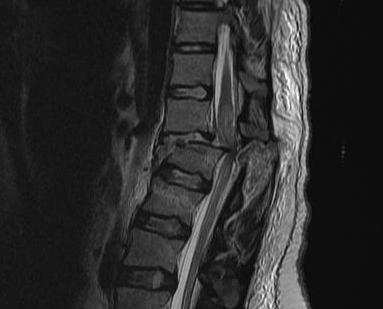

MRI

Advantage

- defines level of conus

- may need anterior rather than posterior surgery if lesion above conus

- HNP

- cord signal change

- assess posterior ligament integrity

- assess level of conus medullaris